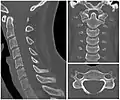

X-ray of cervical vertebrae